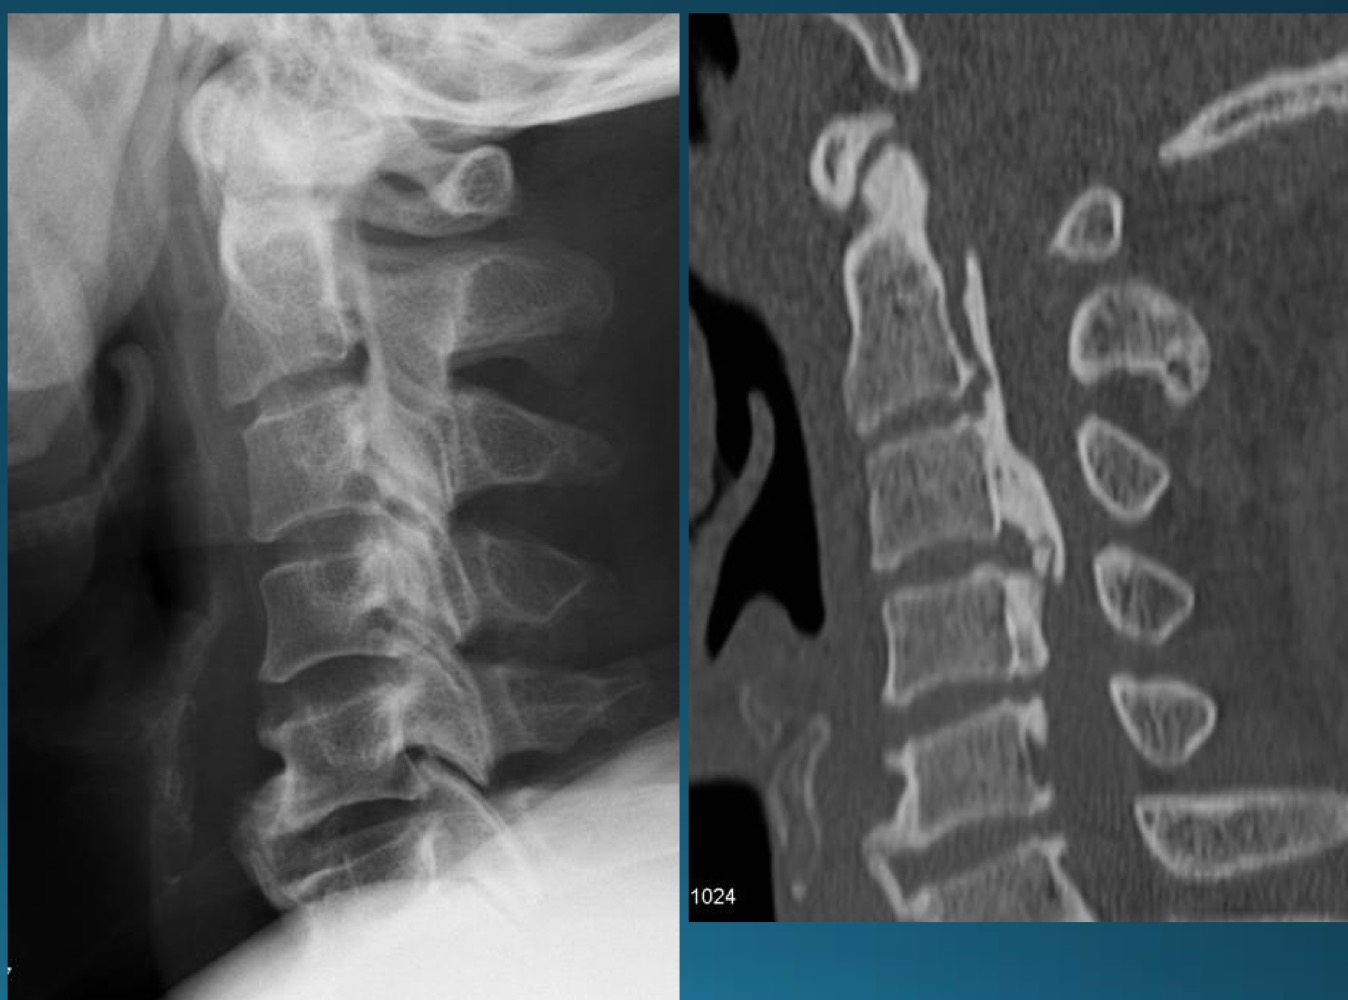

what degenerative joint disease is only found in the cervical spine

uncovertebral joint arthrosis

what are the findings in this image?

what do you call the radiographic feature commonly seen in uncovertebral joint arthrosis

pseudofracture

facet arthrosis